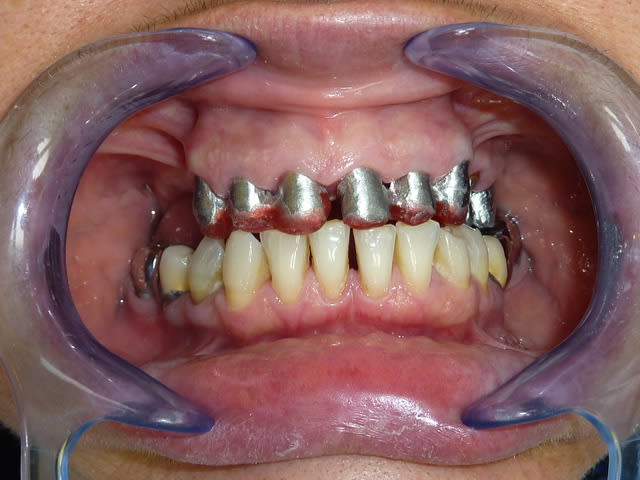

Mais la, apres 1 an de traitements reguliers, entre les lambeaux d'assainissements, les élongations coronaires et les reprises de traitements pourrave j'ai enfin BOUCLE CE CAS !

Pour l'egression des dents mandibulaire le patient ne voulait SURTOUT pas toucher au dents encore "saines" .

"Chaques fois qu'on ma touché une dent j'ai eu un probleme donc si elles n'ont rien touchez les pas svp "dixit le patient. En augmentant la DV de 4 mm j'ai pu eviter les meulages.

Le probleme c'est que maintenant il ne les trouvent pas belles et veut les blanchir/meuler... Sont jamais content les patients.

Pourquoi blanche : toujours selon le patient . "Dr j'ai eu les dents pourris toutes ma vie, aucun dentiste n'a voulu me soigner . Si vous me faites quelque chose je veux que se soit blanc" Amen

C'est les dent 31-41-42-43 qui sont jaunes au max, c'est pas les courones qui sont blanches !

Je ne comprenais pas le plan de tx de 31 à 43...mais si c'est le patient qui décide...

Céramique : A l'orgine le patient n'en avait strictement rien a foutre de l'esthetique . Laisser ces 4 dents saines , meme jaunes, n'empechait pas de réaliser tout le reste . Alors si le patient le veut et que je peux il n'y avait aucune raison de toucher a ces dents (sauf peut etre pour les canadiens :) ).